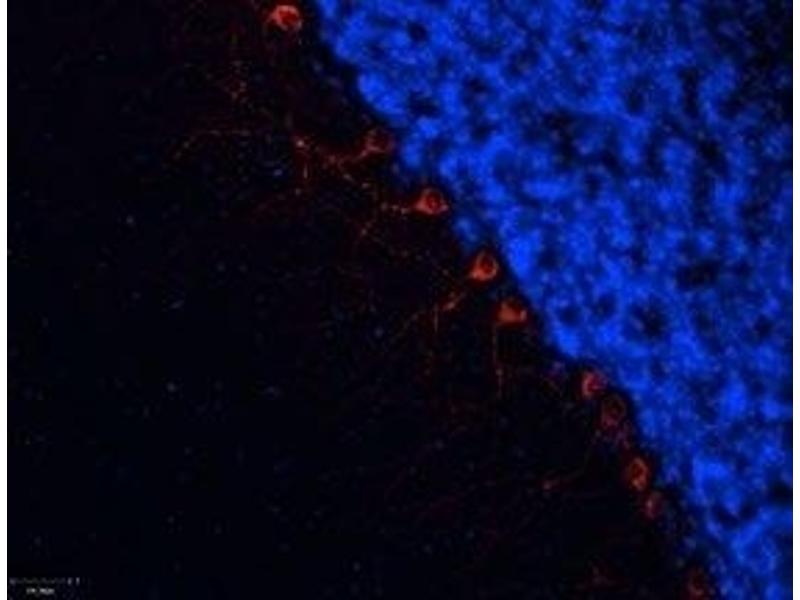

Synthetic peptide, A Blocking peptide for Anti-α1B-Adrenergic Receptor (extracellular) Antibody (ABIN7042897, ABIN7043914 and ABIN7043915) and Anti-α1B-Adrenergic Receptor (extracellular)-ATTO Fluor-488 Antibody (ABIN7042898). Intended to be used as a negative control.